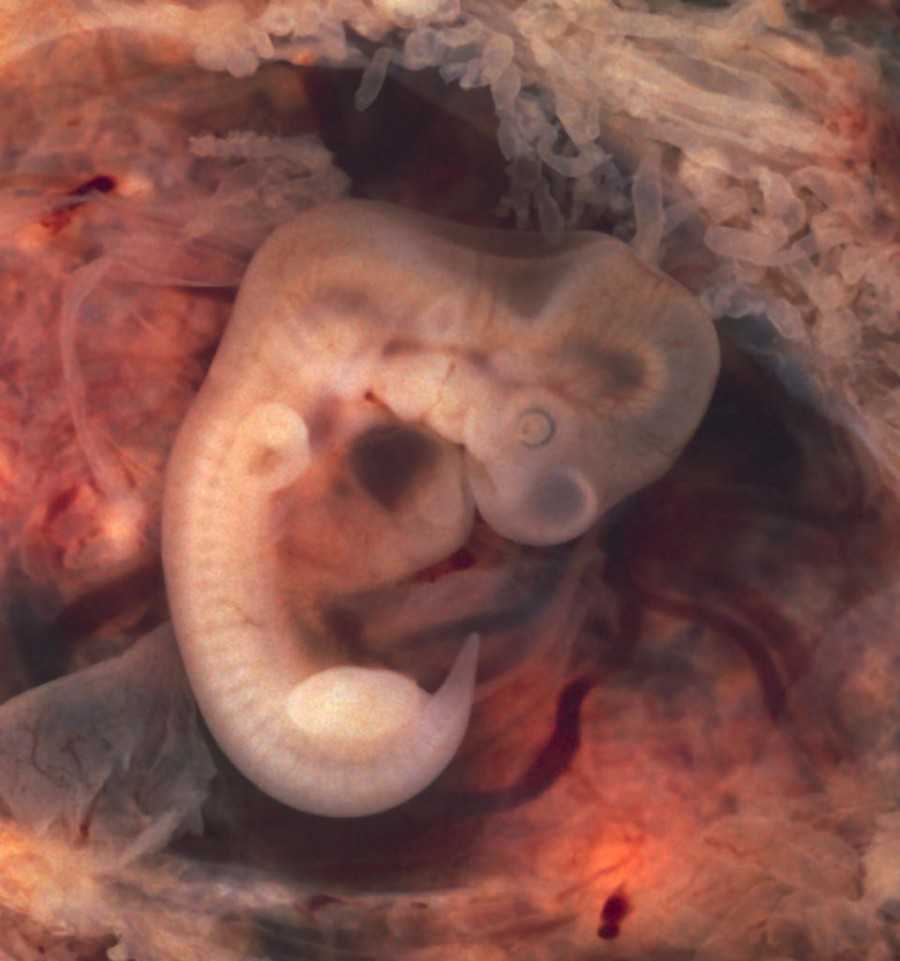

Конечно, больше всего будущим родителям интересно знать, что происходит с малышом на 8–9 неделе. Он растет, и к этому сроку беременности длина плода уже достигает 2,5 см. Это примерно небольшая виноградинка или вишенка. Он свободно расположен в полости матки. При этом вес его составляет 4 грамма. Но, несмотря на небольшие размеры, при проведении ультразвукового исследования, у малыша уже можно различить личико и половой бугорок.

Также на врач может увидеть и сообщить родителям много другой полезной информации, а также показать плод на мониторе, присоединенном к датчику УЗИ. Эмбрион на 9 неделе жизни выглядит как человек, явно различимы голова, лицо с носиком и губами, ушные раковины, тельце, ручки и ножки с маленькими пальчиками. Но у ребенка все есть небольшой хвостик, а пропорции тела далеки от пропорций взрослого человека, и даже новорожденного. Голова эмбриона гораздо больше и доминирует над телом.

У ребенка развиваются мышцы, поэтому его движения становятся более скоординированными. Он может запрокидывать голову, шевелить пальцами, руками и ногами. Также печень малыша начинает синтезировать эритроциты, видны мочеточники, работают почки, развивается лимфатическая система. На УЗИ четко определяется сердцебиение эмбриона. На этом сроке мозг ребенка уже начинает работать, поэтому ребенок шевелится в ответ на внешние раздражители.

Продолжается формирование мозга: появляются гипофиз, мозжечок. На сроке 9 недель начинает работать пуповина, которая соединяет организмы мамы и ребенка, передает эмбриону все необходимые для нормального развития микроэлементы и витамины, а также уносит продукты жизнедеятельности плода.